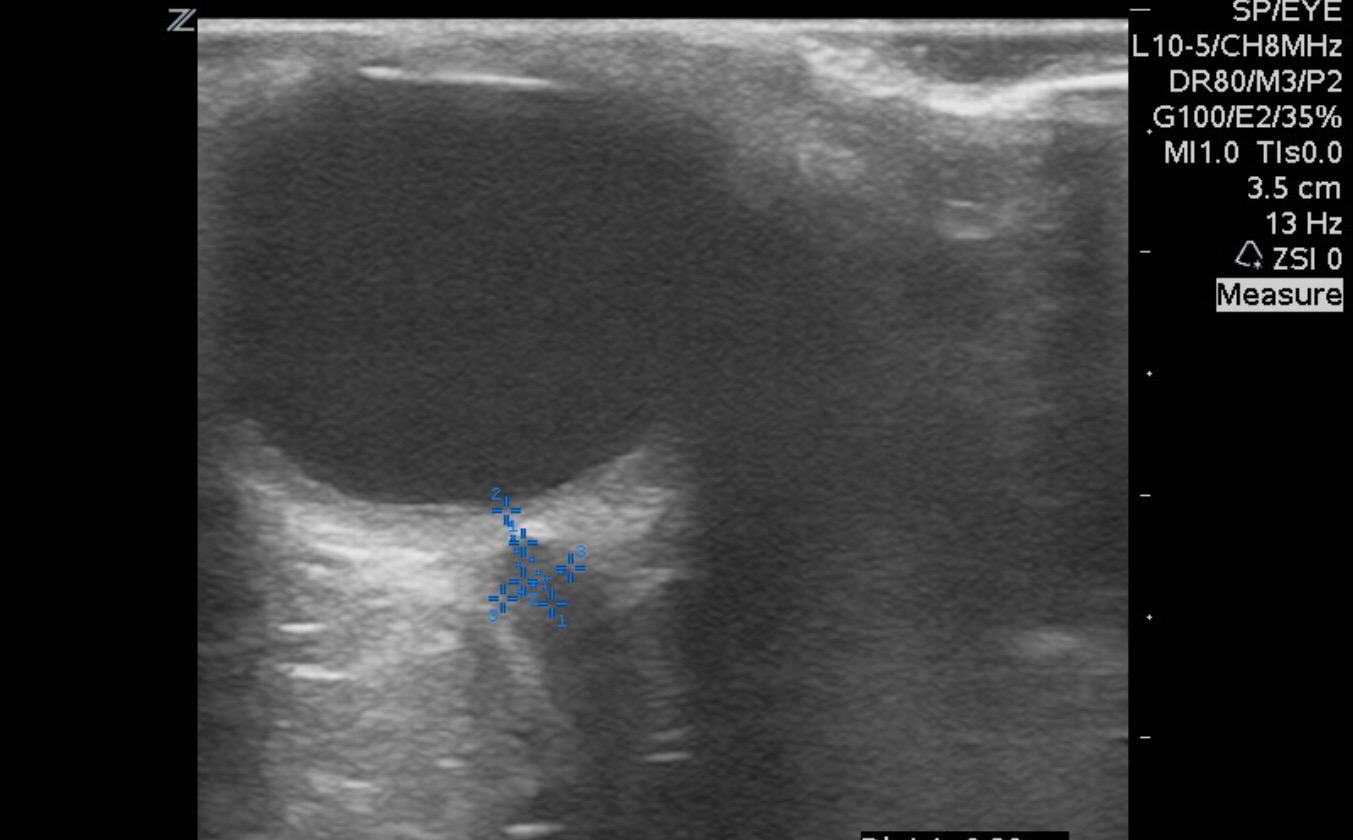

So close, but a few too many measurements. When evaluating for optic nerve sheath diameter or ONSD measure 3mm from the retina into the optic nerve. Then measure the diameter left to right. A value of more than 5mm in adults suggests an elevated intracranial pressure.